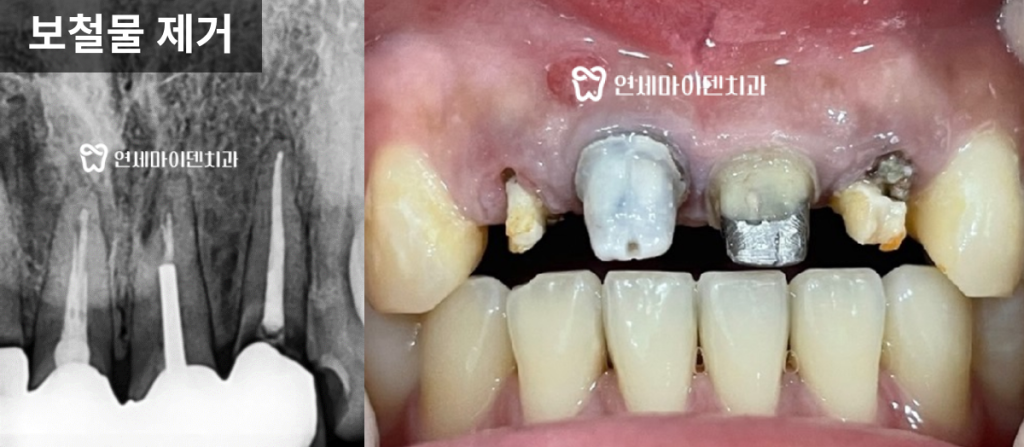

내부에는 깊은 충치가 진행돼 있었습니다.보철물을 제거하자 치아 내부 조직이 심하게 손상되어 있었고,

결국 보존 불가로 판단했습니다.

이에 따라 발치 후 즉시 임플란트를 진행했습니다.

다행히 치조골 상태가 양호해 즉시 식립이 가능했습니다.